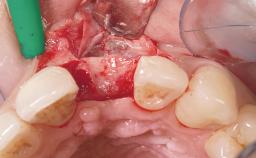

Immediate Placement of an Implant in a Maxillary Left Central Incisor Site

A 33-year-old female patient presented with an upper left central incisor that required extraction after a failed endodontic therapy. The tooth had been traumatized when the patient was a teenager and had undergone several endodontic treatments, including two apicectomy procedures. The patient was in good health and did not smoke. Clinical examination showed that the patient had a high lip line. In full smile, the gingival margins of the upper teeth were visible to the first molars. The gingival margins of central incisors 11 and 21 were only just showing. Examination of tooth 21 confirmed that the tooth was mobile and had hypererupted by 1 mm.

Soft Tissue Grafting Simultaneous

Soft Tissue Anatomy Intact Defective